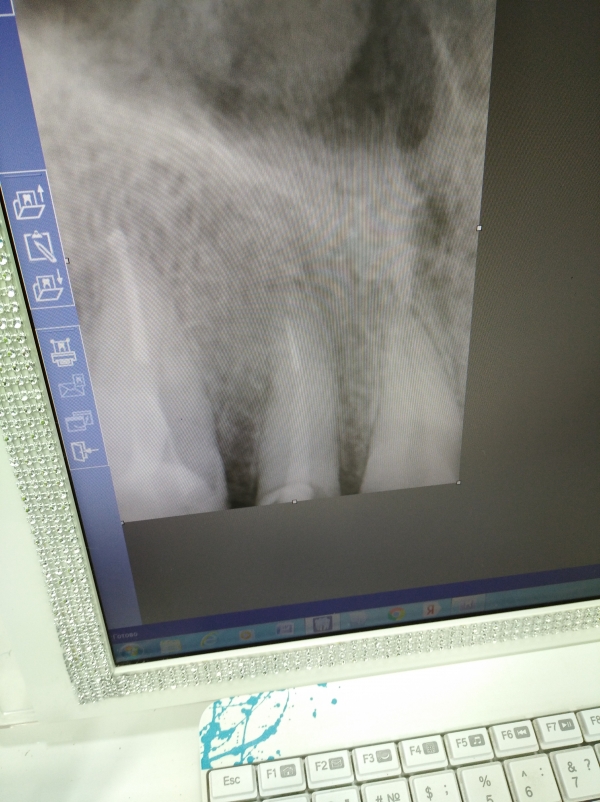

На снимке проблемный зуб (между центральным и клыком). Этот зуб был восстановлен штифтом и пломбой. Недавно с этого зуба откололась пломба ниже десны, но штифт на месте.

Можно восстановить такой зуб коронкой или без импланта не обойтись?